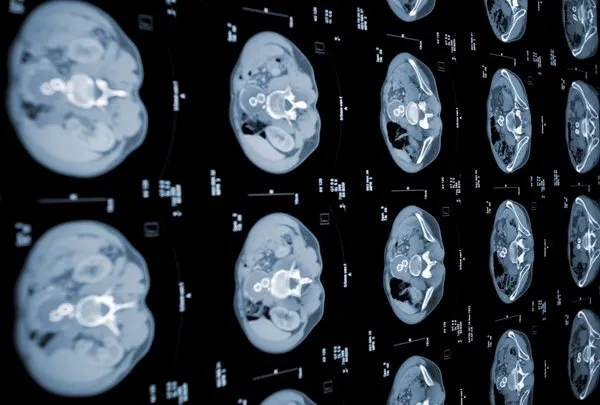

Pankreas kanserinde tümör teşhisi için. 11 22 pankreas kanseri neden olur. Bunun nedeni pankreastaki tümörün insülin üretimine engel olmasıdır. Pankreasın herhangi bir yerinde kanser görülebilir bu nedenle pankreas kanseri kendi içerisinde üç kısma ayrılır.

Pankreas kanseri pankreasın herhangi bir yerinde bulunan bir kanserdir. Pankreas kanseri birtakım diyabet belirtileri ile karşılaşmanıza da neden olabilir. Pet pankreas kanseri nedir. Pankreas kanseri tipik olarak yakındaki organlara yayılım gösterir.

Petrol ürünleri ve diğer kimyevi maddelerle çalışanlarda pankreas kanseri gözlenmektedir. Tespiti çok da kolay olmayan pankreas kanseri pankreastaki sağlıklı hücreler hızla çoğalmaya başladıkça ortaya çıkar. Pankreas kanseri organın her kısmında görülebilmektedir fakat en fazla görüldüğü bölüm baş bölgesidir. Bu mutasyonlar hücrelerin kontrolsüz bir şekilde büyümesine ve normal hücrelerin ölmesinden sonra yaşamaya devam etmesine neden olur.